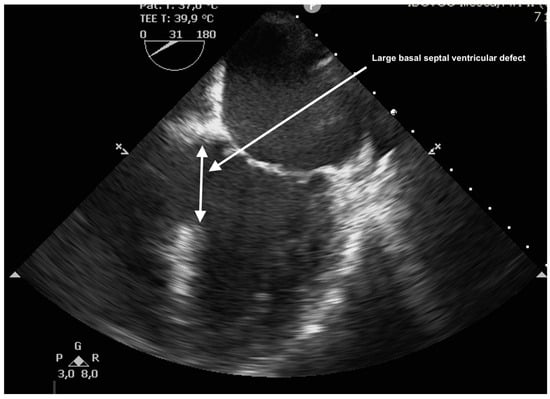

The case was discussed in the multidisciplinary heart team (cardiologist, interventional cardiologist, cardiac surgeon, anesthesiologist) and, after informed consent, it was decided for a watchful waiting tactic, planning a delayed repair. Preoperatively, the patient was evaluated with a transesophageal echocardiography (TEE) for better defect characterization and MR quantification (Figure 3 and Figure 4). Percutaneous defect closure was deemed technically unfeasible due to the anatomy of the defect, which was located at the base of the septum and involved the mitral valve apparatus, while also exhibiting significant mitral valve regurgitation.

Figure 3. TEE showing large basal VSD.